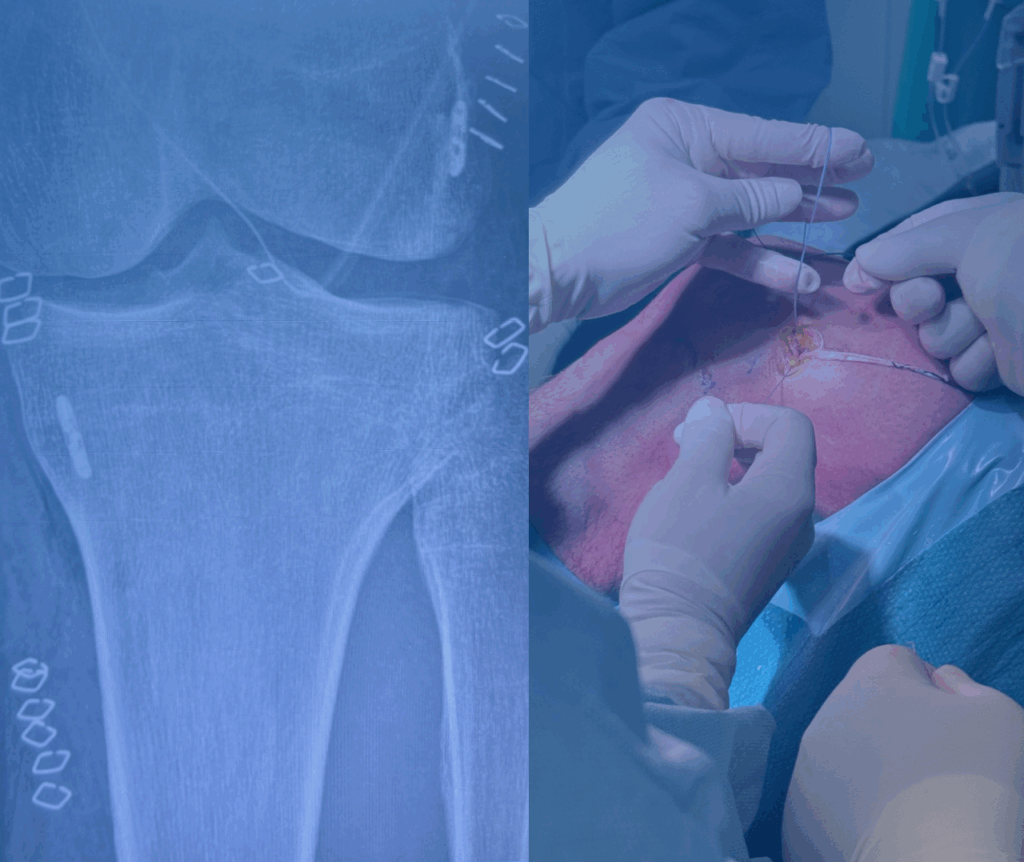

Si svolge nella ricerca scientifica e nella pratica chirurgica in linea con l’evoluzione di tecniche sempre meno invasive, per la cura delle patologie della spalla, del ginocchio, della caviglia e del piede.

Mettersi in discussione costantemente attraverso lo studio, la ricerca e il confronto con professionisti nazionali e internazionali permette di esercitare una chirurgia sempre più moderna e personalizzata con risultati sempre più sicuri.